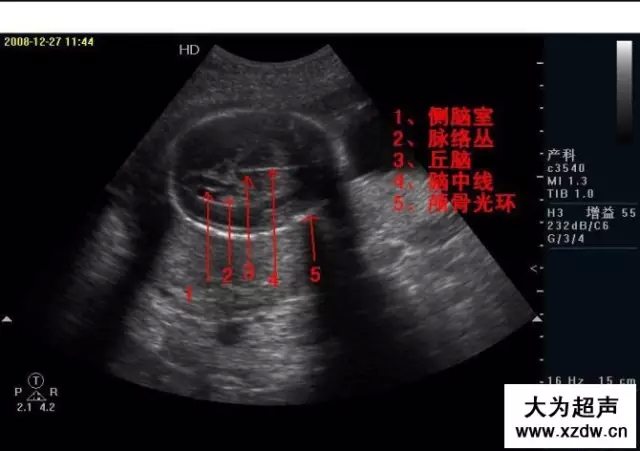

產(chǎn)科超聲正常圖片